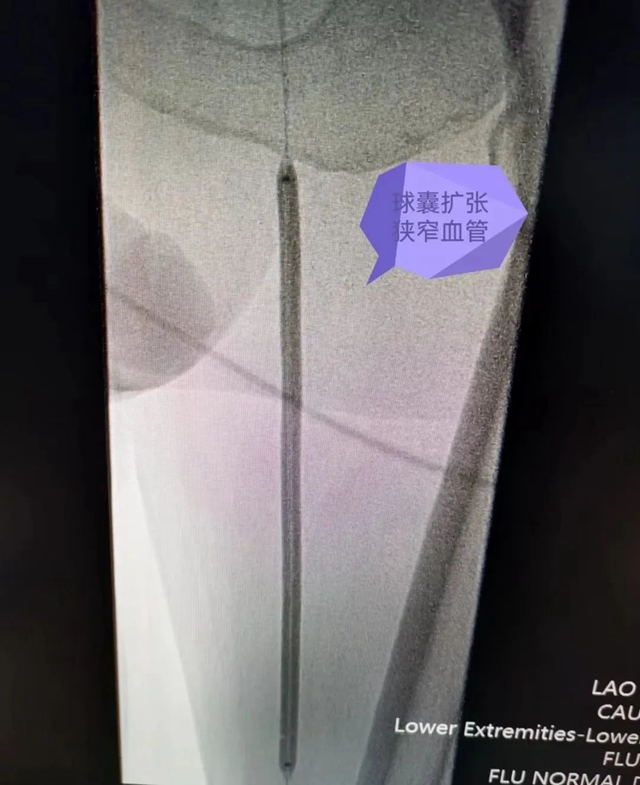

术中对狭窄段进行球囊扩张